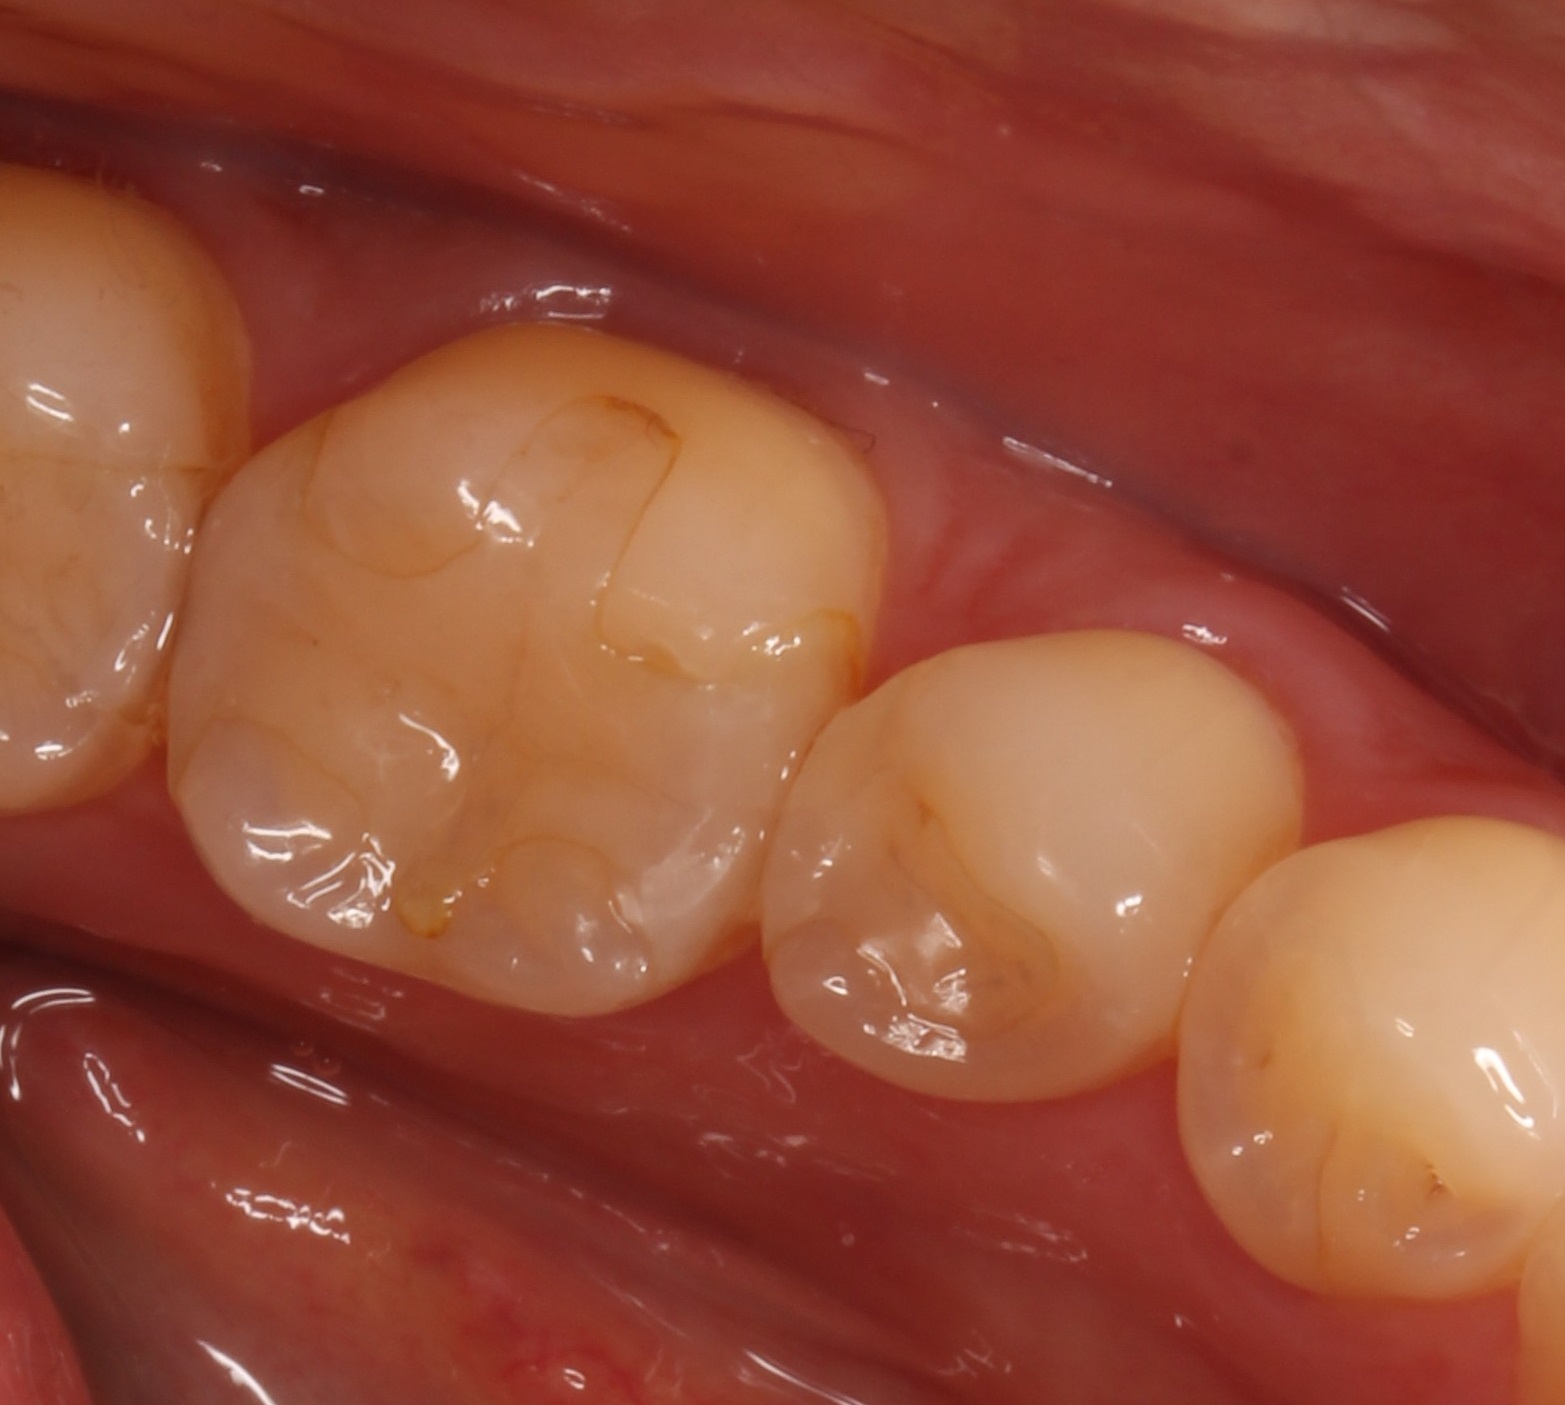

セラミック?が欠けた?よくあるトラブル

• Before